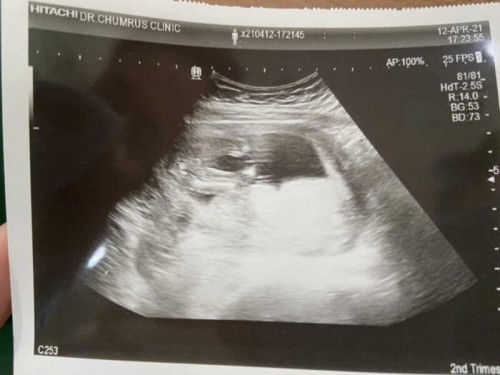

ซาวด์เพศ 16w+6d

แม่ๆ ดูให้หน่อยค่ะ ญ. ไหมคะ ที่บ้านอยากได้ผญ.มากค่ะ ลุงหมอซาวด์นานมากๆ ไม่เจอจู๋ ลุงหมอบอก ญ. 90% 😍 #ดีใจมากค่ะ #จู๋จะโผล่มาไหมคะ 😂

อันนี้ช่วยดูให้หน่อยค่ะ ว่าได้เพศอะไรค่ะ หมอบอกยังไม่ชัวร์

ถ้าได้ญ.ก็ดีเลยค่ะ ขอบคุณนะค่ะ

ผุ้หญิงจ้า มีกลีบ2กลีบ

ญ ค่ะ